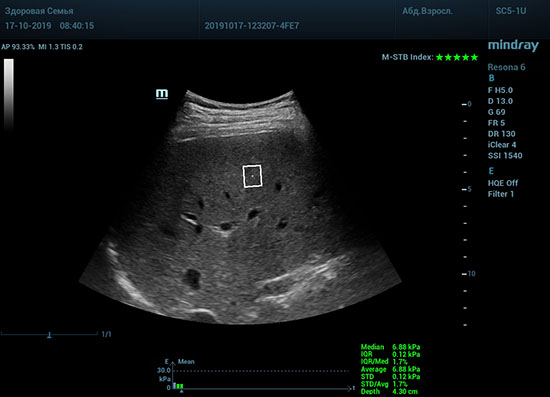

Датчик посылает ультразвуковую волну способную сжать участок паренхимы печени. В момент расправления тканей органа после сжатия, происходит образование поперечные волн. Для их регистрации, следом за волной сжатия, посылается регистрирующая волна, которая улавливает изменения скорости. Закономерность изменения скорости позволяет использовать модуль Юнга для оценки плотности ткани. Таким образом мы получаем аналог FibroScana’а, который упоминается в рекомендациях по диагностике и лечению жировой болезни печени, фиброза и цирроза. Разница в том, что теперь не нужно приобретать отдельный прибор. Все уже есть в ультразвуковой системе. Быстрее, дешевле, доступнее. Так же исчез пугающий пациента эффект «удара» типичный для фиброскана. Методика, в отличии от биопсии, не инвазивная и может применяться даже у детей.

Определение плотности печени. Не ошибся ли оператор при измерении эластических свойств печени? Для оценки критериев качества предусмотрен индекс MBT, который покажет насколько «твердой» была рука оператора и двигалась ли печень. При MBT 5* рука тверда и показатели достоверны. Для оценки качества результатов используется IQR индекс, отображающий колебания показателей в точке измерения при расчете медианы. Показатели при IQR <30% считаются приемлемыми. Техника сканирования через межреберные промежутки требует размещение окна интереса на несколько сантиметром ниже капсулы, для исключения эффекта реверберации. Установка ROI на паренхиму без захвата сосудов, для исключения погрешностей измерения.

Стадия фиброза определяется по системе METAVIR Staging, построенной на данных биопсии и сопоставлении с данными эластографии. Своевременная диагностика фиброза, и начало его лечения, залог благоприятного исхода заболевания.

- METAVIRF0 – норма.

- METAVIRF1 – Портальный фиброз без вовлечения перегородок

- METAVIRF2 – Портальный фиброз с вовлечением нескольких перегородок

- METAVIRF3 – Портальный фиброз с вовлечением множества перегородок

- METAVIRF4 – Цирроз.